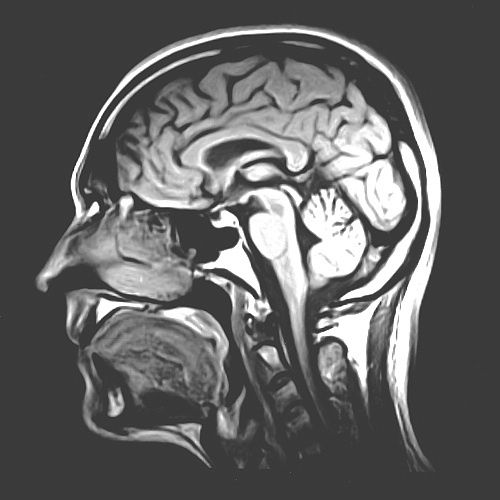

GBM, or glioblastoma, is already one of the deadliest brain tumors. It grows fast and spreads like wildfire, and despite surgery, radiation, and chemo, most people diagnosed with it only live about 14 months. Doctors and researchers are doing everything they can to fight back…

This subtype isn’t just another face in the crowd. It’s the troublemaker of the GBM family. While all GBM tumors are aggressive, mesenchymal GBM comes with its own toolkit of genetic mutations that make it especially nasty. It mutates tumor suppressor genes like NF1 and PTEN, which normally help control cell growth and death. Without them, cancer cells have free rein to survive, grow, and invade healthy brain tissue like an evil army on a mission.